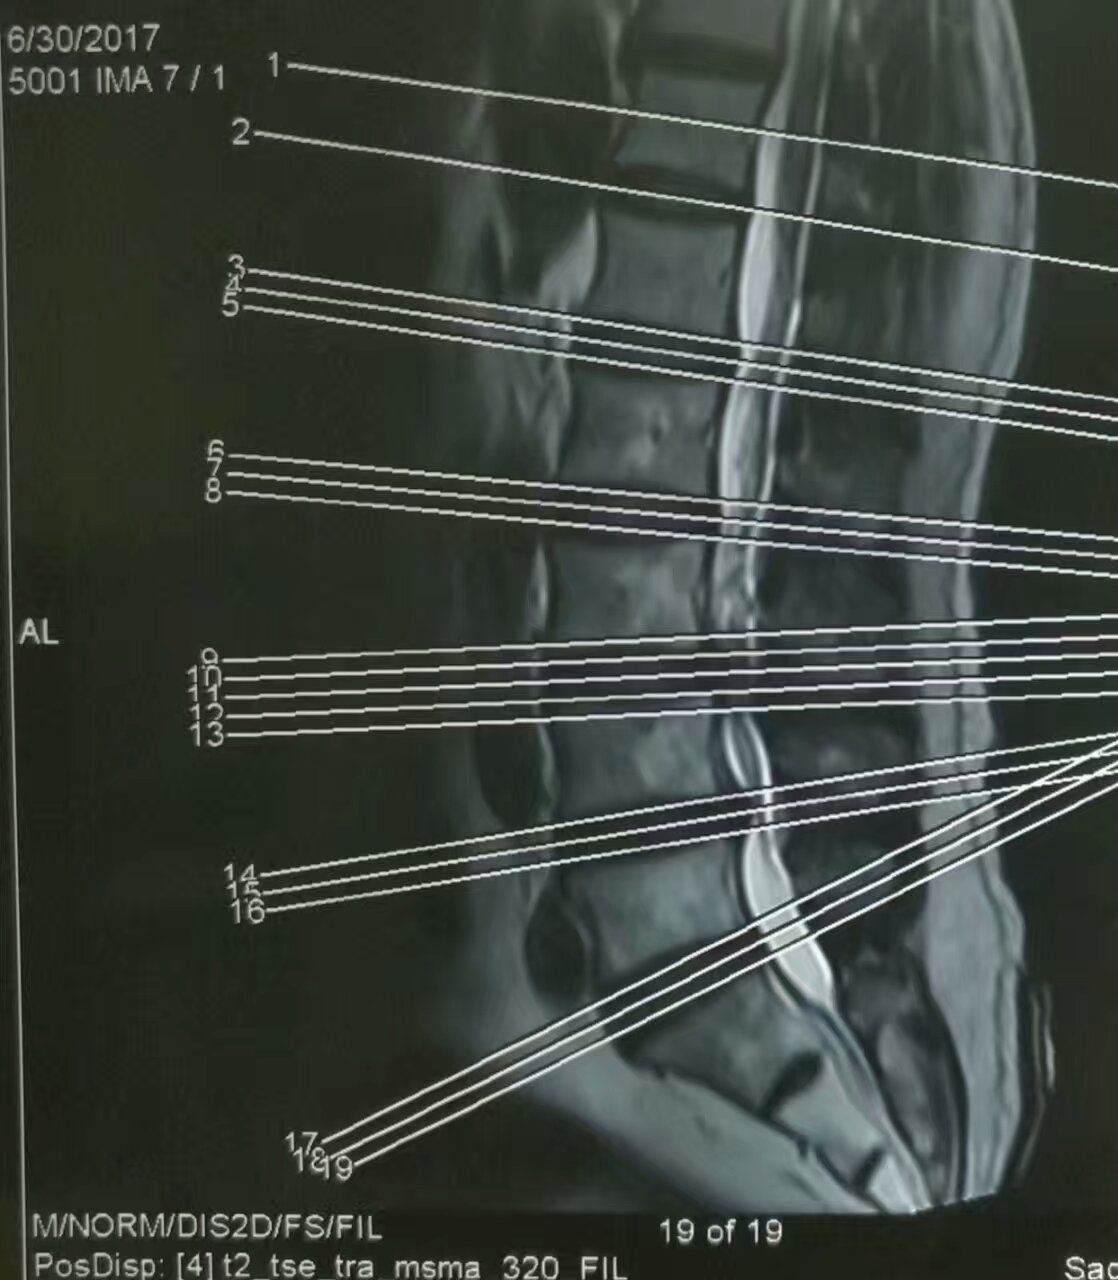

陈某,男,62岁,弧刃射频针治疗腰4、5椎间盘突出症。

赵某,男,47岁,17年前曾行开放性手术后好转,后间断反复慢性腰痛,两月前再次复发加重,间歇性跛行,影像学等检查,考虑腰5骶1椎间盘突出症,顺利弧刃射频针联合臭氧微创髓核消融治疗。